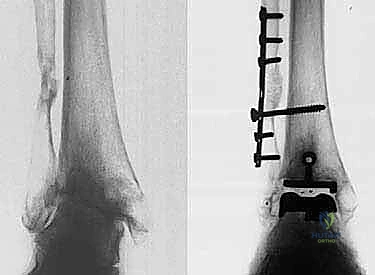

- الأشعة السينية (X-rays) بوضعية الوقوف: وهي الأداة الذهبية للتشخيص. صور الأشعة والوزن محمل على القدم (Weight-bearing X-rays) تظهر بدقة مدى تآكل الغضروف (ضيق المسافة المفصلية)، وجود نتوءات عظمية (Osteophytes)، وأي انحراف في المحور الميكانيكي للساق.

* التثبيت: هو مفصل "غير إسمنتي". يتم تغطية الأسطح المعدنية الملامسة للعظم بطبقة مسامية من التيتانيوم وهيدروكسي أباتيت (Hydroxyapatite). هذه الطبقة تشجع العظم الطبيعي للمريض على النمو داخل مسام المفصل (Bone Ingrowth)، مما يوفر تثبيتاً بيولوجياً صلباً يدوم لسنوات طويلة.